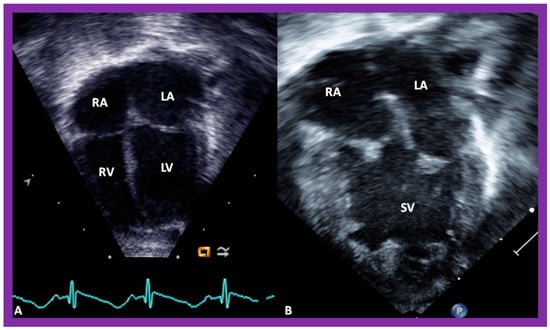

In theory, patients with cardiac malposition may have one (single) or two ventricles. The distinction between one and two ventricles is feasible by echocardiography (Figure 30) and angiography (Figure 31 and Figure 32).

Figure 30. Selected pictures from apical four-chamber echo views of two children, the first (A), who has two ventricles, and the second (B), who has one (single) ventricle (SV). The left atrium (LA), left ventricle (LV), right atrium (RA), and right ventricle (RV) are labeled. Reproduced from reference [4].